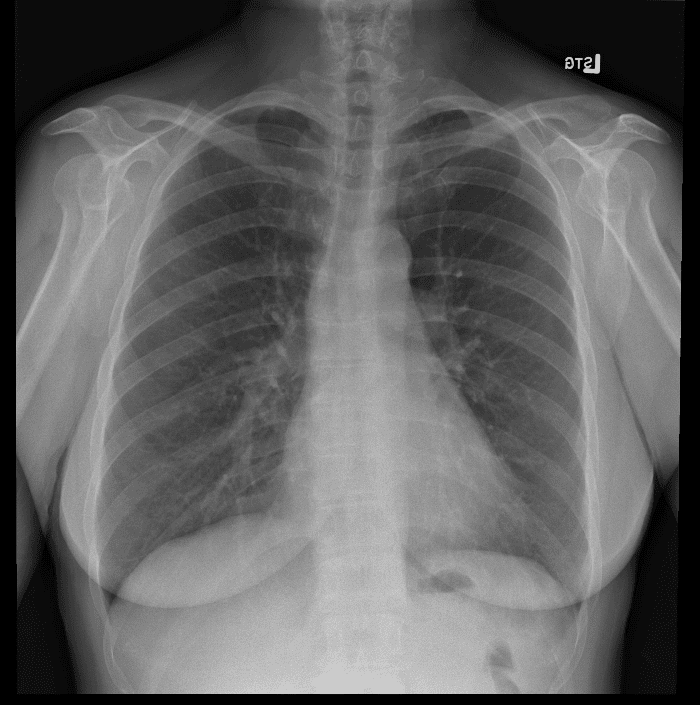

Practice Cases